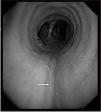

Los traumatismos torácicos son la causa más frecuente de las lesiones traqueobronquiales. Sin embargo, las debidas a maniobras de intubación son menos frecuentes pero potencialmente graves. Estas lesiones pueden producirse durante las maniobras de una intubación difícil, intentos repetidos y con el uso de estiletes o guías de intubación. La lesión de la vía aérea es una complicación rara tras la intubación traqueal, pero puede ser letal. Se presenta el caso de una paciente de 46 años intervenida de una colecistectomía laparoscópica que padeció una laceración traqueal después de una intubación traqueal con una guía Frova. La lesión se manifestó por hemoptisis, enfisema subcutáneo y mediastínico en el postoperatorio inmediato. El tratamiento fue conservador gracias a una evolución favorable de los síntomas y sin secuelas posteriores.

Chest trauma is the most frequent cause of tracheobronchial injury. Less common but potentially serious are lesions caused during intubation maneuvers in a difficult airway, during repeated attempts, or with stylets or other introducers. Though rare, airway lesions are life-threatening complications. We describe the case of a 46-year-old woman undergoing laparoscopic cholecystectomy whose trachea was injured during intubation with a Frova introducer. The lesion manifested with hemoptysis and subcutaneous and mediastinal emphysema early during recovery. The lesion resolved with conservative treatment and there were no sequelae.